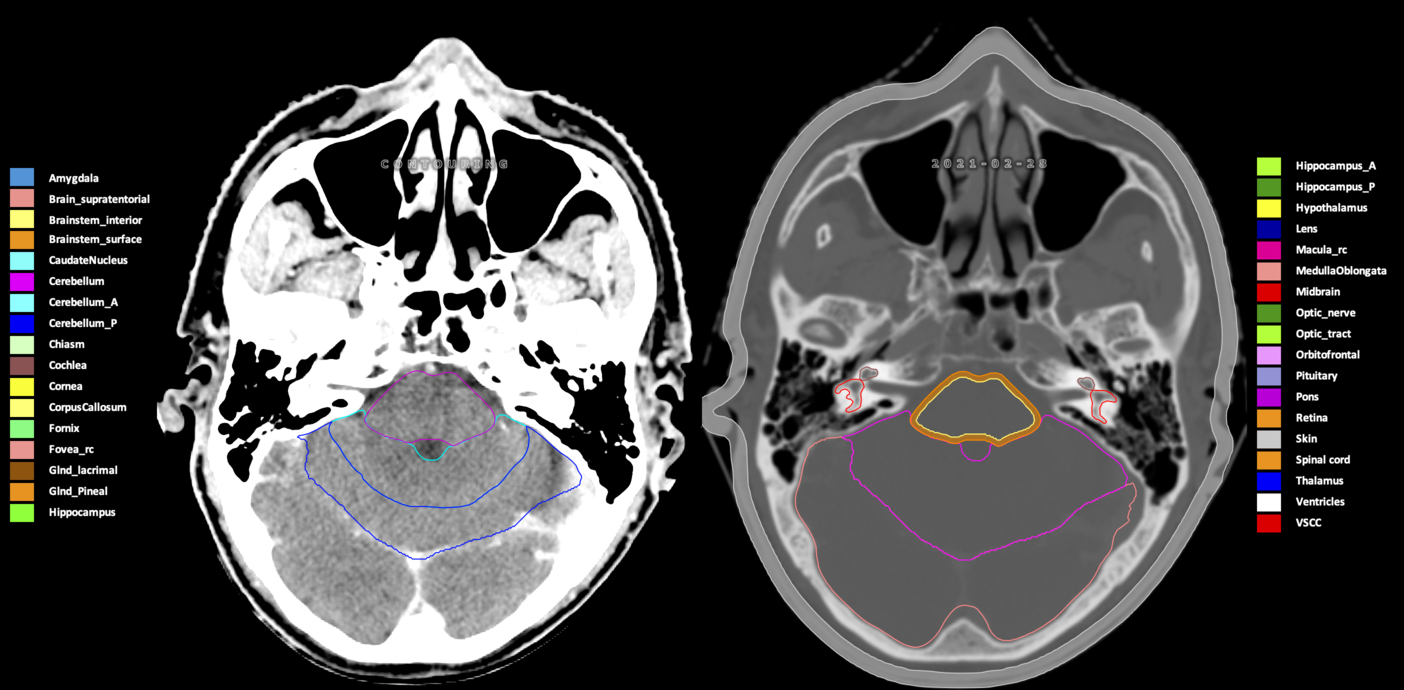

Included are all OARs known to be relevant for radiation-induced toxicity in neuro-oncology: brain, brainstem (midbrain, pons, medulla oblongata), chiasm, cerebellum (anterior & posterior), cochlea, cornea, hippocampus (anterior & posterior), hypothalamus, lens, lacrimal gland, optic nerve, pituitary, skin, and vestibular & semicircular canals. To further facilitate research on cognition, vision and radiological changes after irradiation of the brain, potential clinically-relevant OARs are included: amygdala, caudate nucleus, cerebellum (anterior & posterior), corpus callosum, fornix, macula, optic tract, orbitofrontal cortex, periventricular space (PVS), pineal gland, and thalamus.

Three-dimensional delineation of the 25 consensus OARs for neuro-oncology are shown on CT (WW/WL 120/40, 3000/600), 3T MR images, (T1Gd, T2FLAIR 1mm) and 7T MR (MP2RAGE 0.7 mm). All are presented in transversal, sagittal and coronal view.